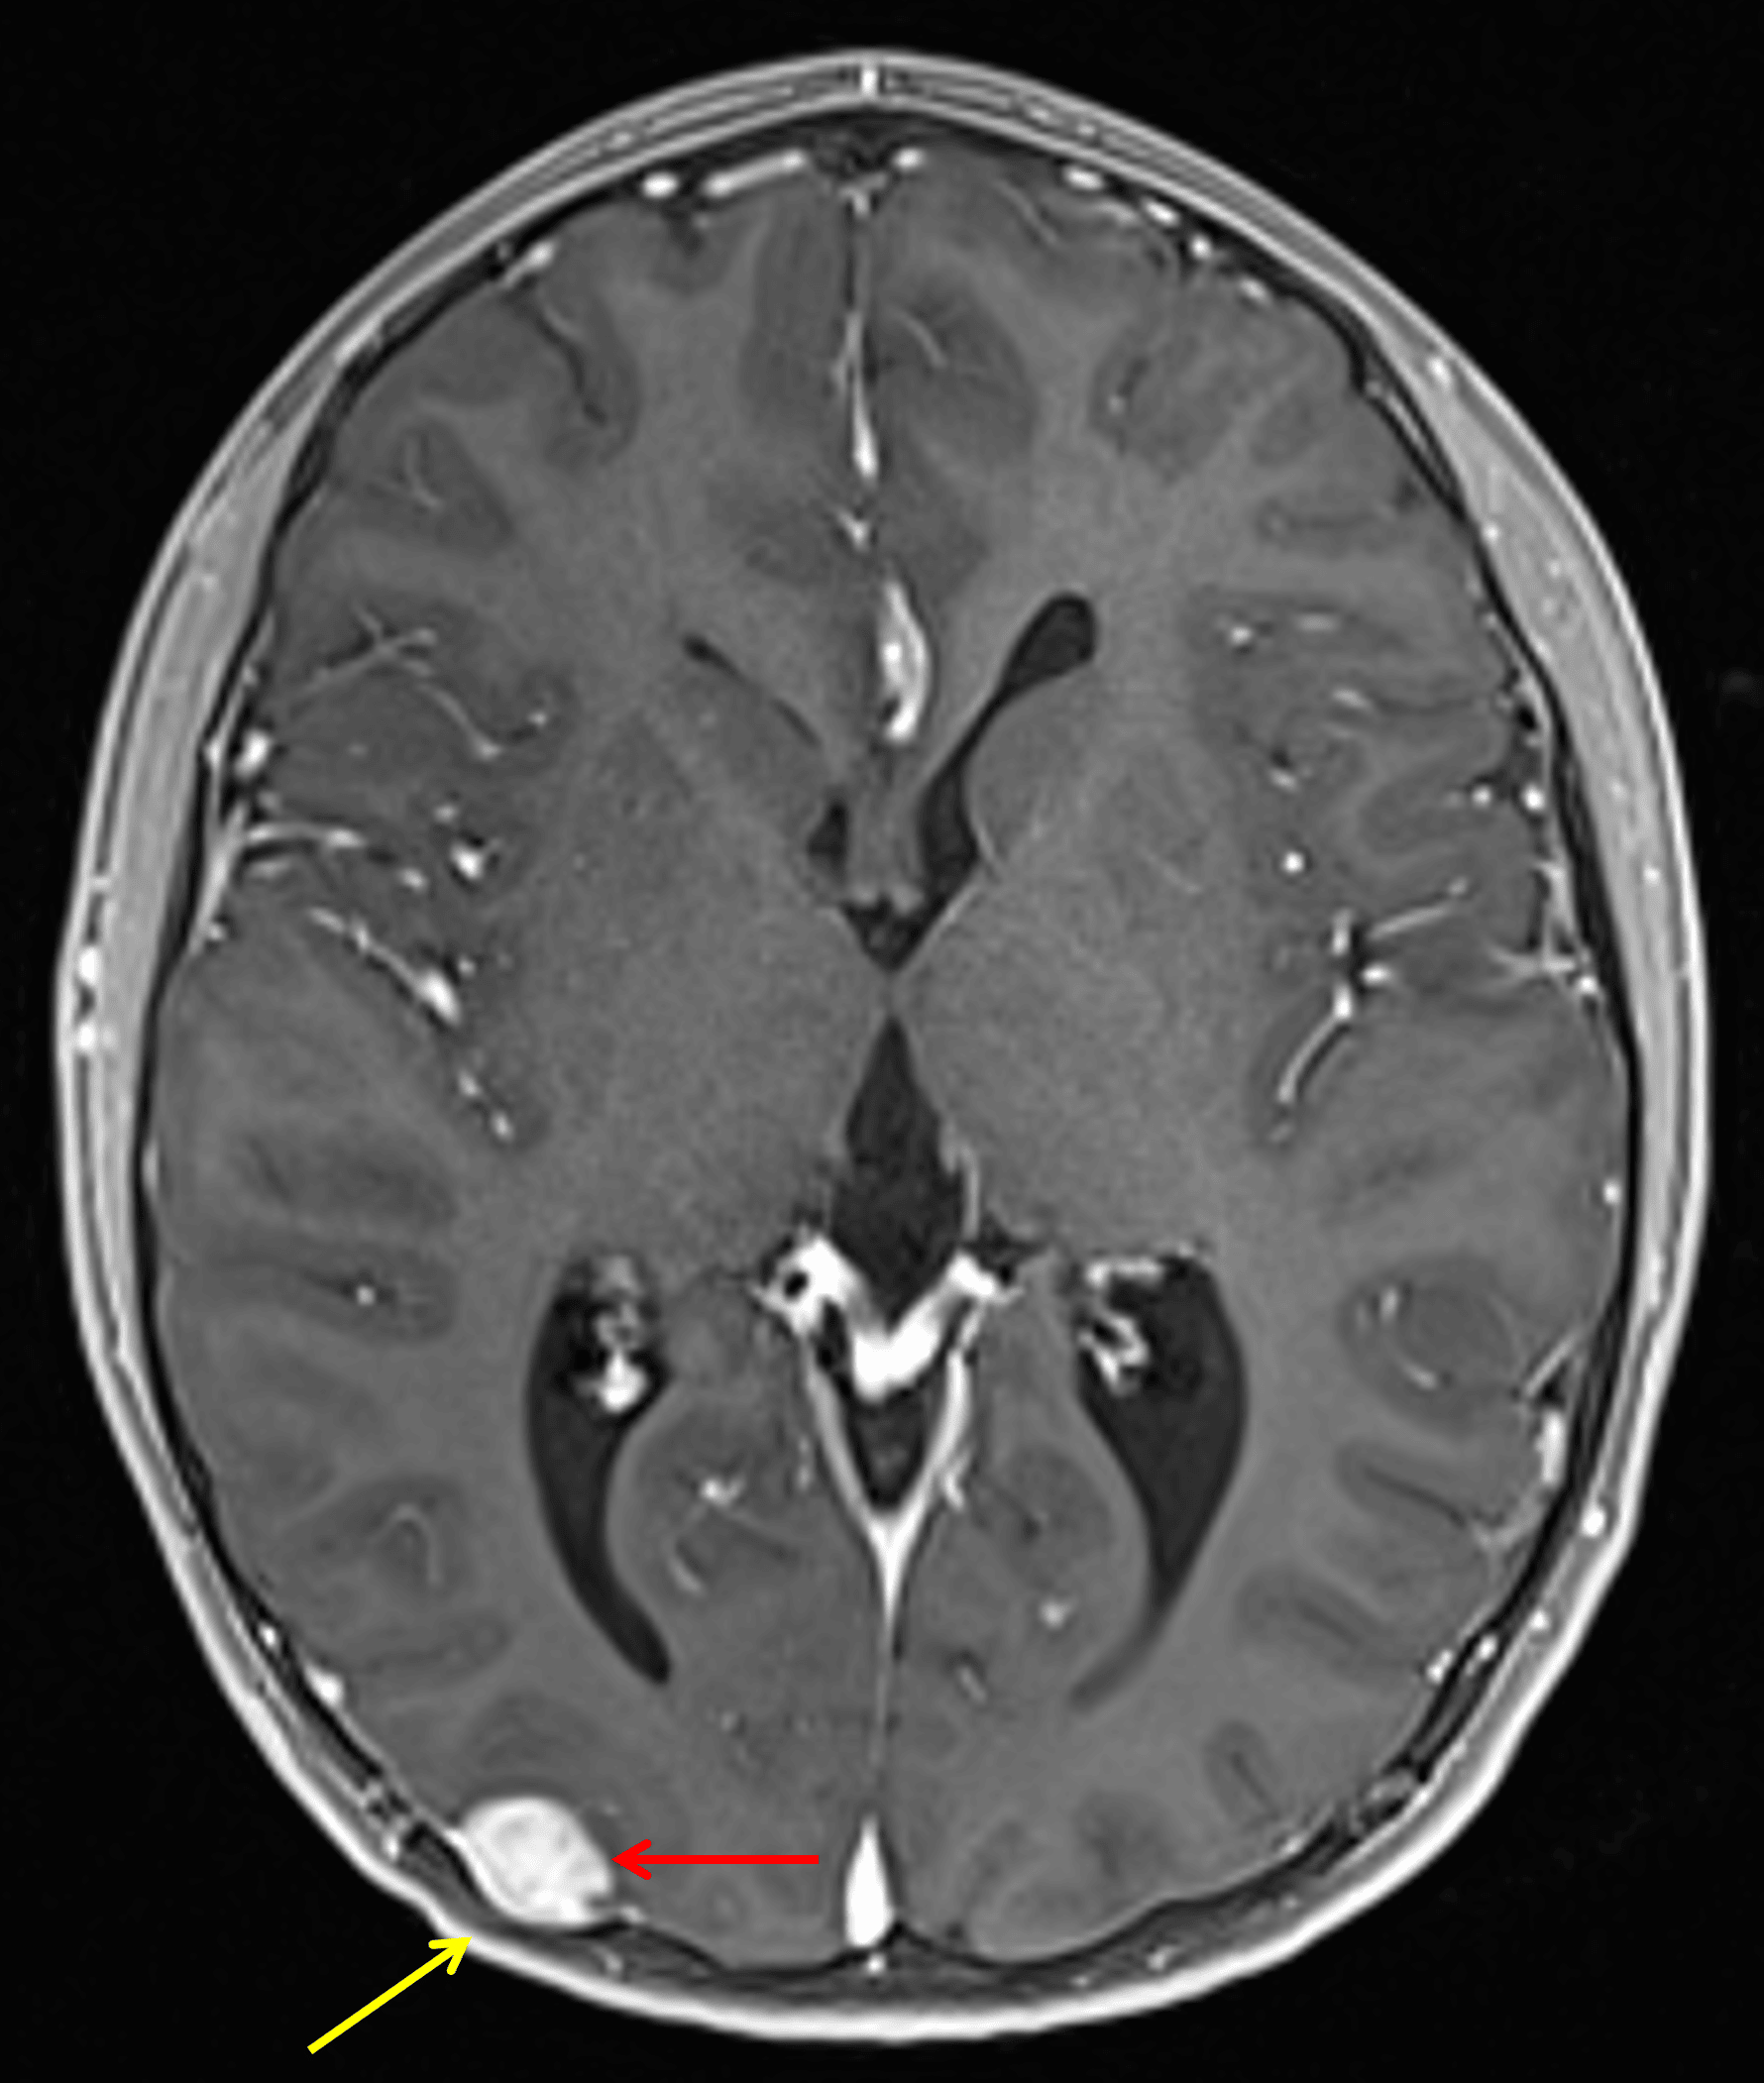

Corresponding nodular enhancement (red arrow) with overlying calvarial scalloping (yellow arrow).